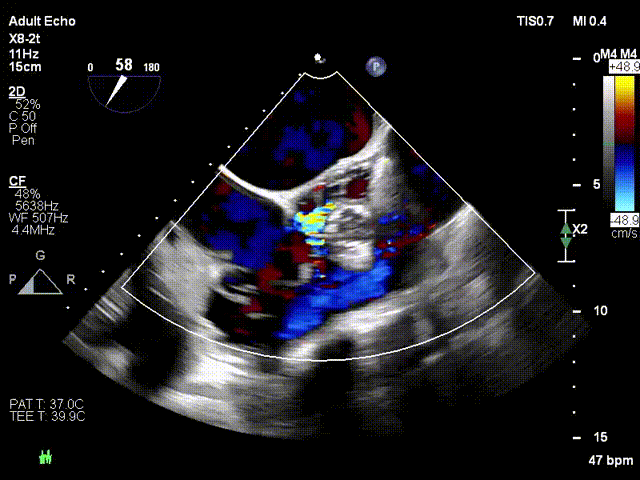

术前超声

术后超声